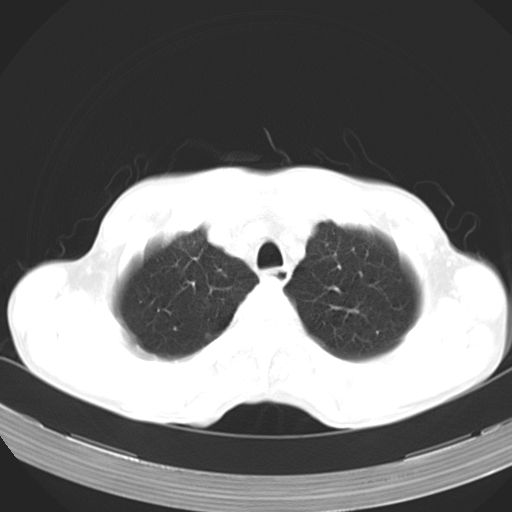

以下是引用zhangzhongshou在2007-5-24 12:55:00的发言:[br]1、右肺中叶中心型肺癌并右肺门、隆突下、纵隔淋巴结转移。右肺中叶阻塞性肺炎。

以下是引用苯小孩在2007-5-24 12:47:00的发言:[br]右侧肺门处不均匀密度软组织块影,远端肺组织见斑片模糊影,纵隔内淋巴结明显肿大,边界不清.<纵隔窗第12层面支气管内似见软组织结节>[br]考虑:1、右侧中央性肺癌并阻塞性肺炎并纵隔淋巴结转移可能性大.建议强化或纤支镜进一步检查.[br]2、隆突下淋巴结肿大/食道病变?请做鉴别检查.

以下是引用jw-830在2007-5-24 15:24:00的发言:[br][br] [br] 考虑右肺中央型肺癌并阻塞性炎症,右肺门及纵隔淋巴结转移。 [br] [br][br]